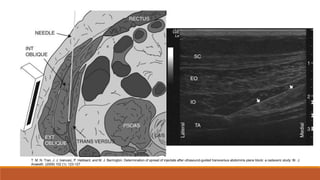

Bloqueo del Plano Transverso Abdominal

TAP

Fibras nerviosas T6-L1

Musculo oblicuo interno y transverso

Por debajo de la fascia que los une

Plano Transverso del Abdomen

T. M. N. Tran, J. J. Ivanusic, P. Hebbard, and M. J. Barrington. Determination of spread of injectate after ultrasound-guided transversus abdominis plane block: a cadaveric study: Br. J.

Anaesth. (2009) 102 (1): 123-127